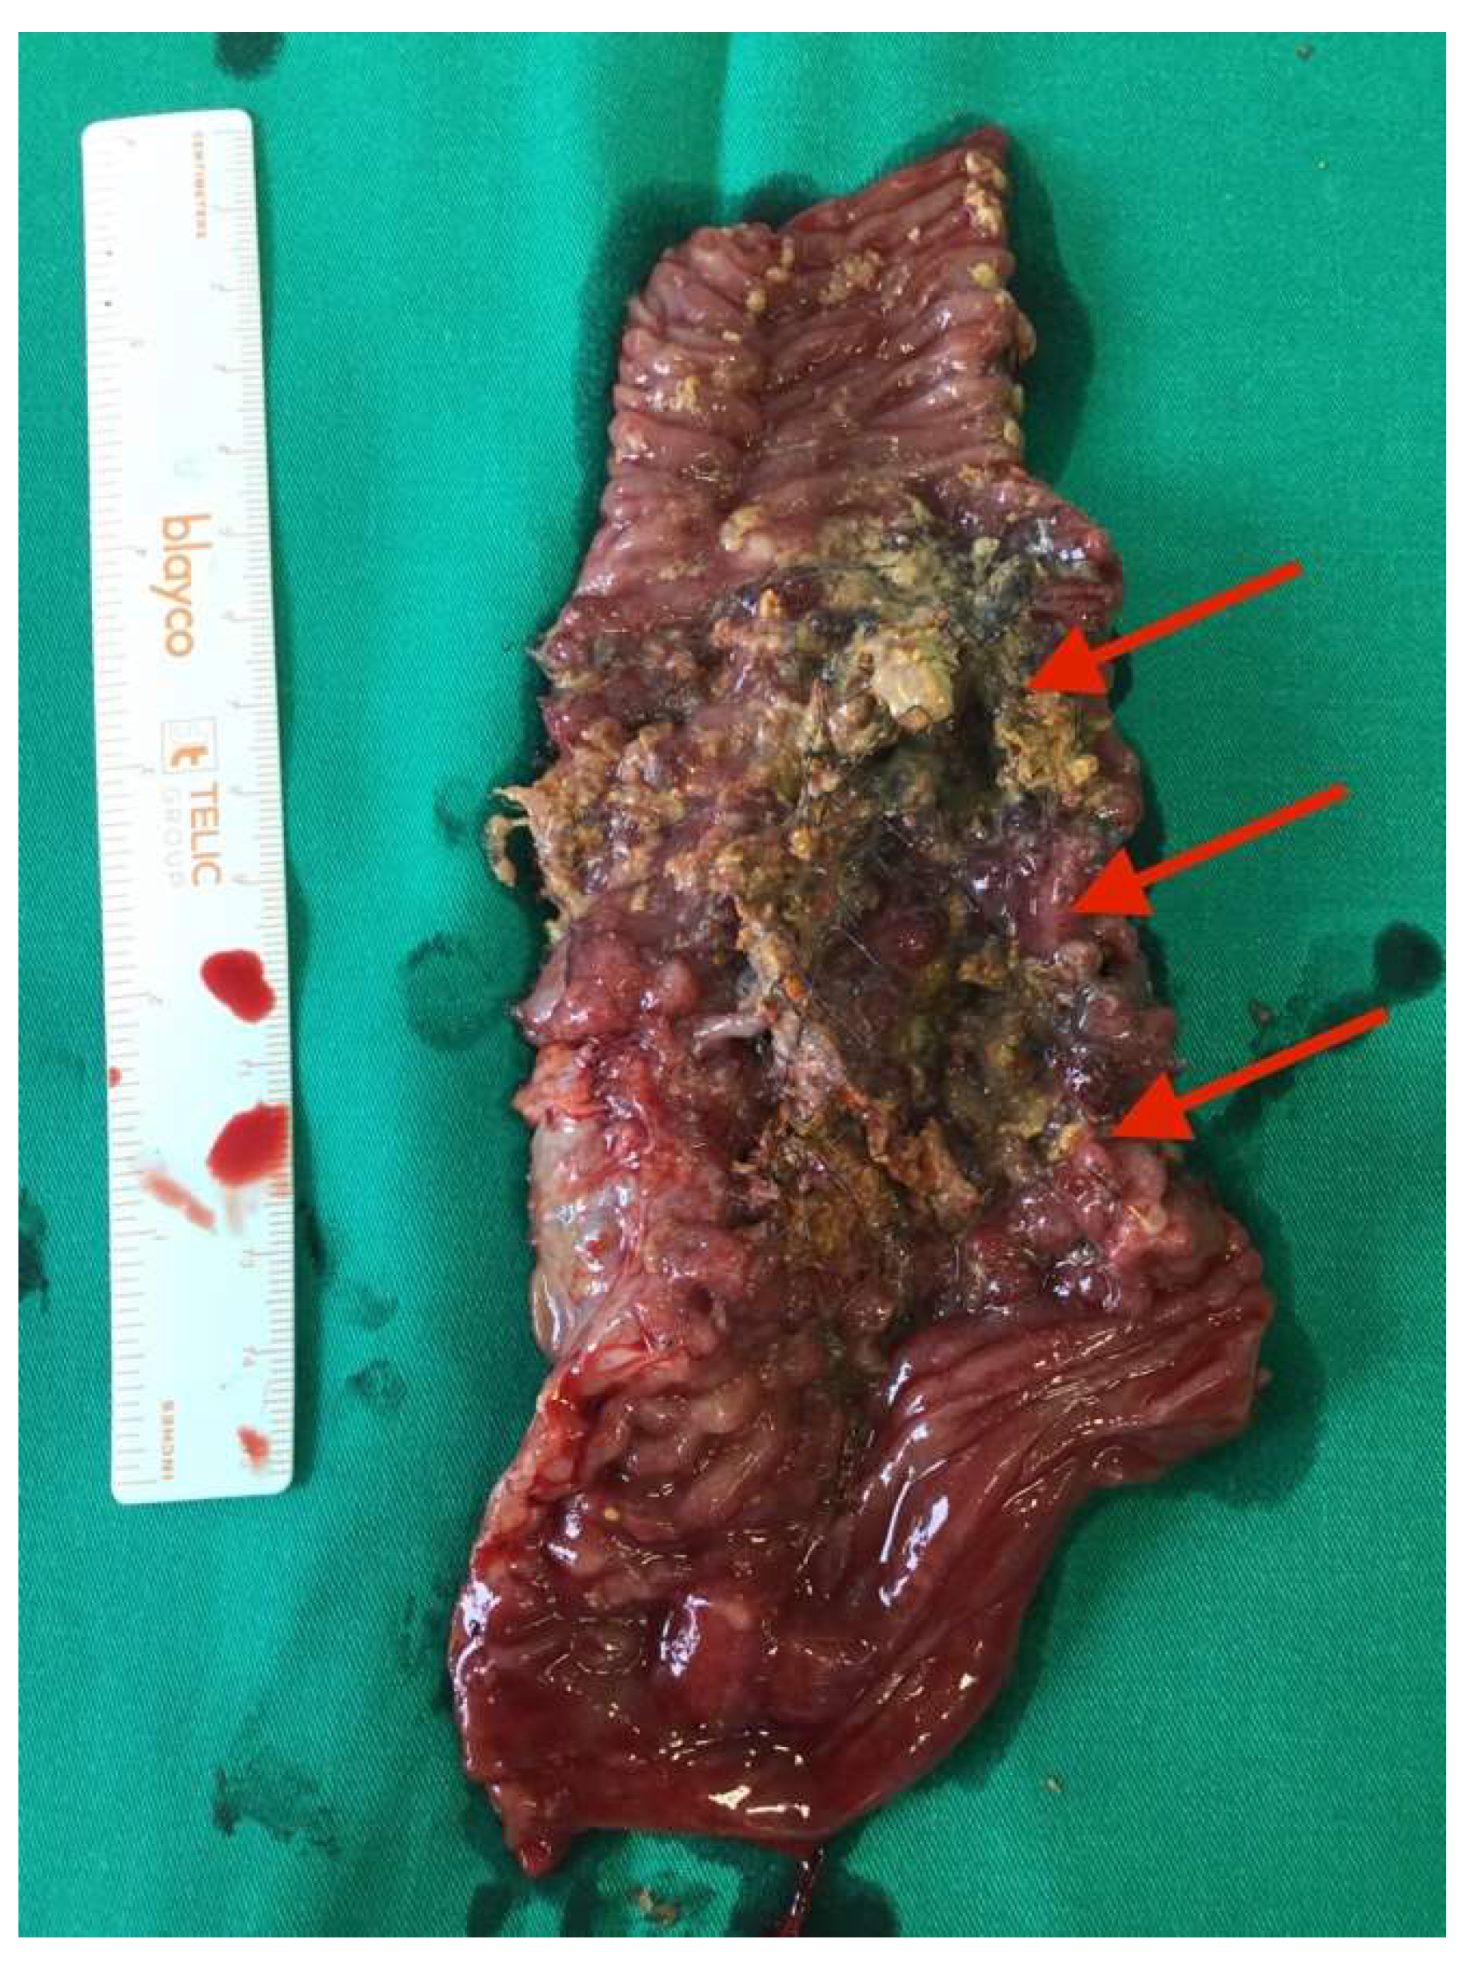

After the optimization of the patient’s nutritional status, a laparotomy, adhaeolysis, and jejunal resection were performed. A conglomerate consisting of the small intestine 80 cm from pl. duodenojejunalis was identified and a metal stent was palpated. The intestines 5 cm proximal to the blockage were found to be hypertrophic and considerably inflated (Figure 2 and Figure 3). The resection of 10 cm of the small bowel with the metal stent was performed and a jejunojejunal anastomosis was formed using a running 3-0 PDS suture (Figure 4).

Histopathological examination of the specimen (13.5 cm portion of the small bowel with an ingrown 7.5 cm metal stent and resection margins of 2 cm and 3.5 cm) revealed a diffuse submucosal lymphoplasmacytic infiltration with lymphoid follicles and polymorphonuclear leukocytes as well as ulcerated granulocytes.

Figure 4. Metal self-expanding stent in the resected portion of the bowel (red arrows).